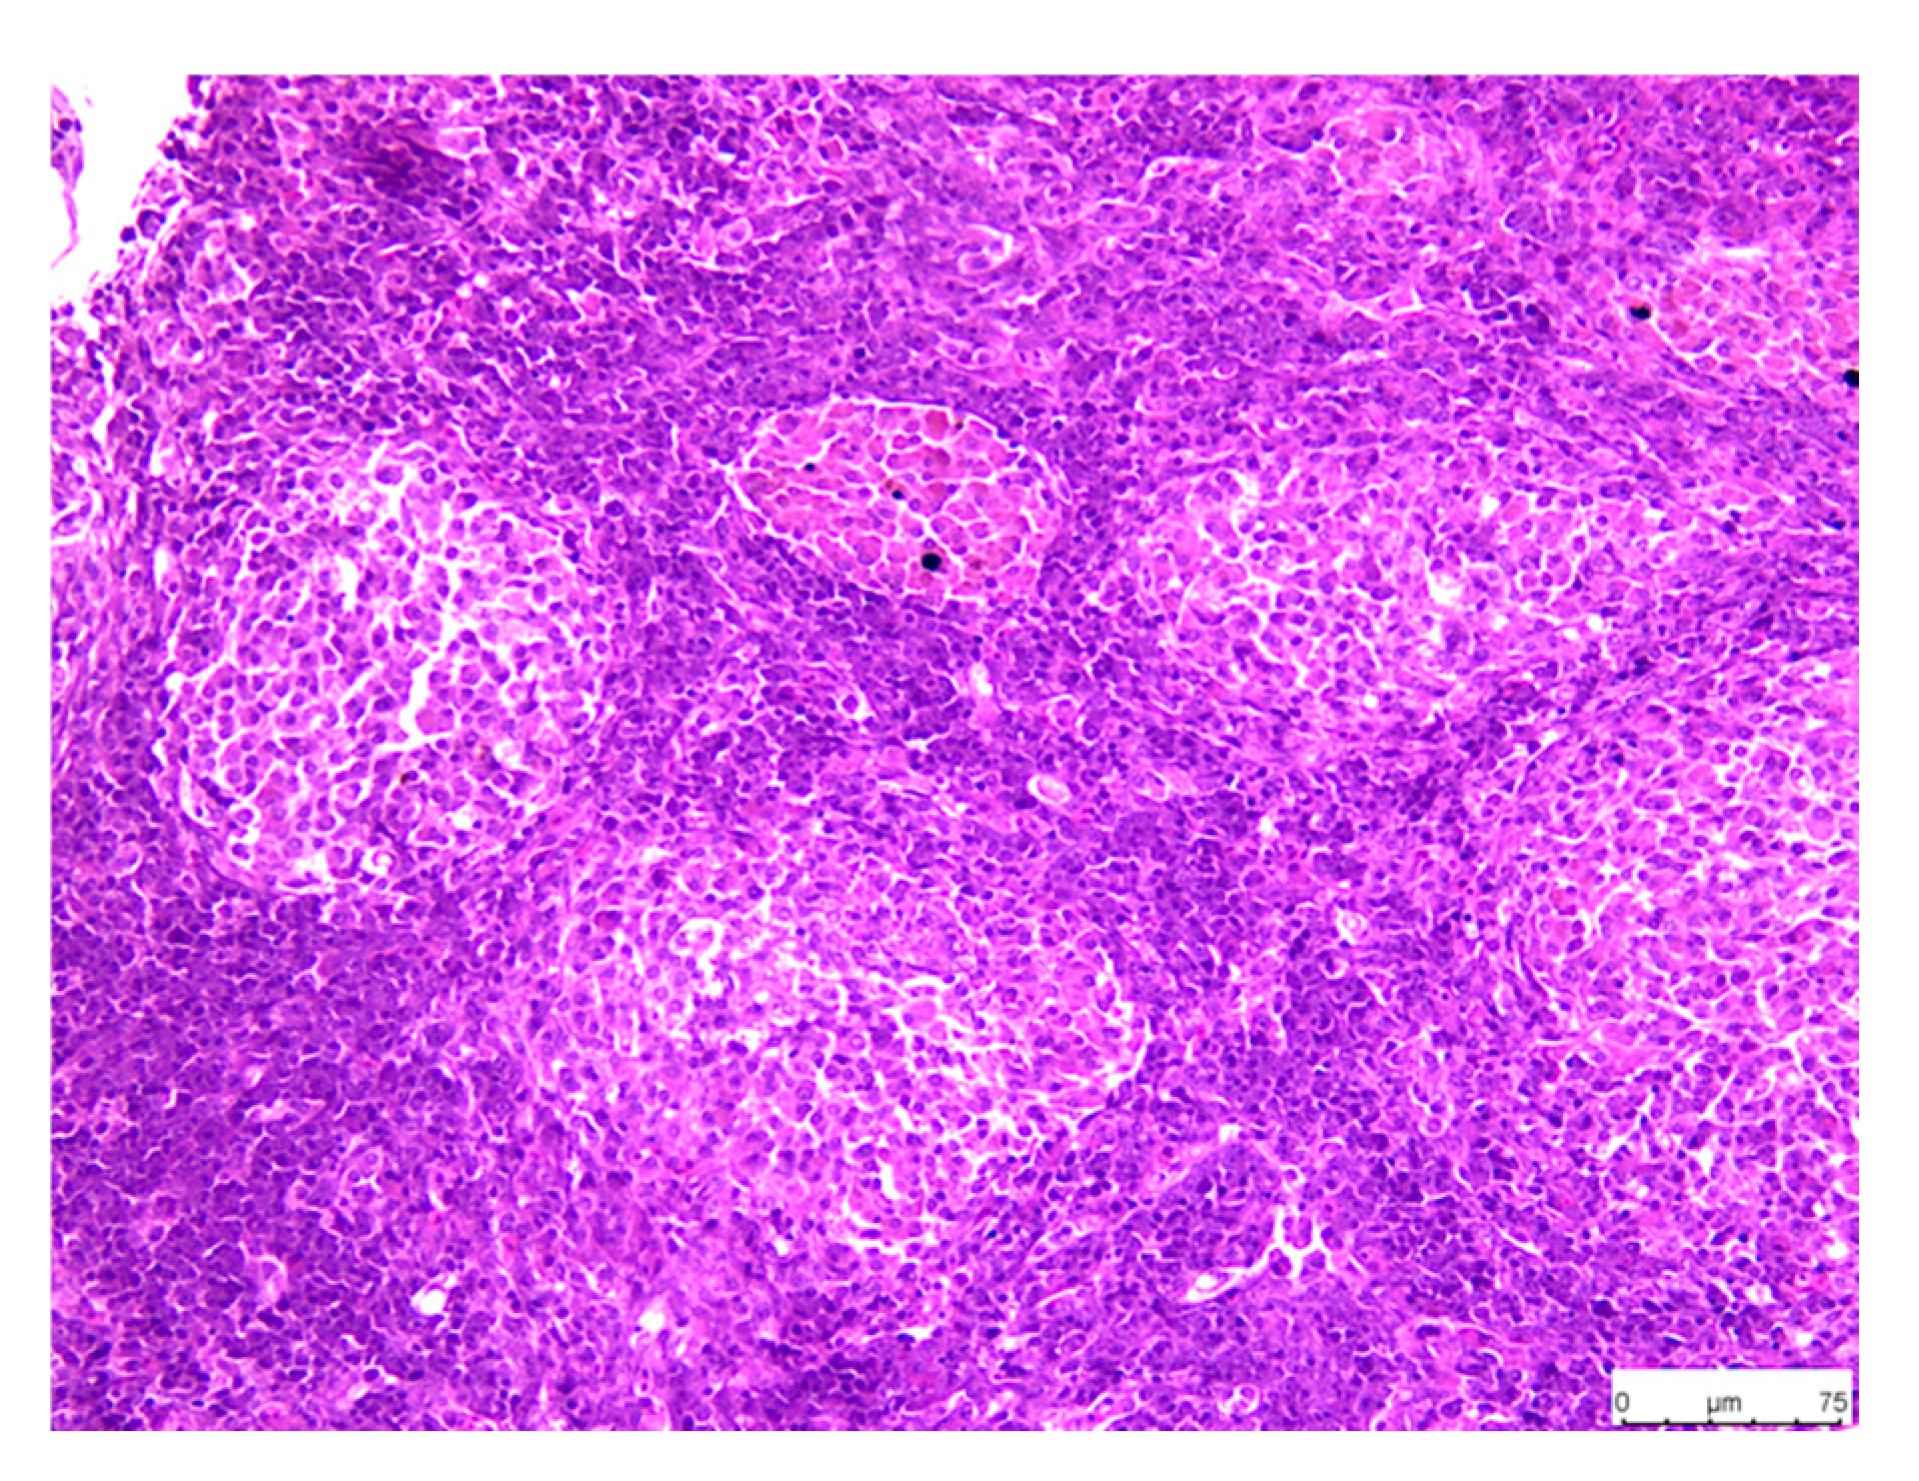

3.3.2. Spleen

3.3.3. Head Kidney